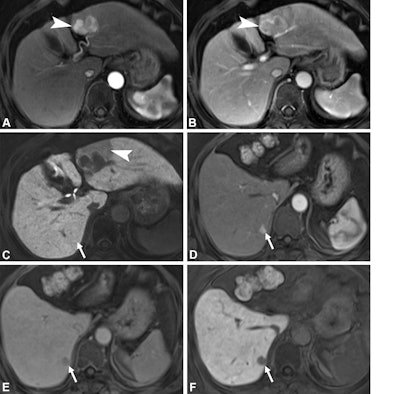

Axial gadoxetic acid-enhanced MRI scans in a 63-year-old woman with recurrent hepatocellular carcinoma (HCC) at 18 months of follow-up and a high MRI-based Early Recurrence Individualized Score (score of 11) show a 4-cm hepatic mass in liver segment 3. (A) Prominent arterial-phase hyperenhancement (arrowhead) is noted with (B) enhancing capsule (arrowhead) in the portal venous phase, consistent with HCC. (C) Hepatobiliary phase image shows nonsmooth tumor margins with wedge-shaped peritumoral hypointensity (arrowhead). The preoperative serum aspartate aminotransferase level is 32 IU/L, higher than the cutoff determined by the Youden index (29.5 IU/L). Partial hepatectomy was performed, and pathologic analysis showed conventional HCC with P53 overexpression but no microvascular invasion. The patient’s Pathology-based Early Recurrence Individualized Score is 8. At the 18-month follow-up, the arterial-phase gadoxetic acid-enhanced MRI scan shows a new focus of arterial hyperenhancement in segment 7 (arrow in D) that was absent on the preoperative MRI scan (arrow in C). The lesion shows portal venous phase washout (arrow in E) and a corresponding hepatobiliary phase defect (arrow in F), consistent with recurrent HCC.RSNA